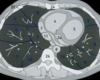

TC ventana pulmonar

Se ven mejor la vía aérea, vasos pulmonares y cisuras, pero todas las estructuras mediastínicas aparecen de un tono gris demasiado similar.

Imagen de TC de alta resolución que muestra fibrosis pulmonar.

Principales utilidades de TC de alta resolución son:

• Valorar el grado de afectación de enfermedades intersticiales pulmonares.

• En pacientes EPOC, para valorar el grado de enfisema y pequeñas zonas de atrapamiento aéreo.

• Determinar la gravedad y extensión de bronquiectasias.

• Valorar qué área es más rentable biopsiar.